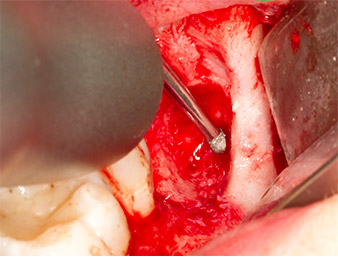

The tissue above the root remnant was not completely ossified and consisted for the most part of granulation tissue modified by inflammation (Fig.4).

To obtain autogenous material for subsequent wound treatment, healthy bone chips were harvested from the surroundings of the root remnant with a piezo surgical instrument (Piezomed B5) (Fig. 5).

The autogenous tissue was removed with the scraper-shaped section of the working part of the instrument and stored in a physiological saline solution until further use (cf. Fig. 13).